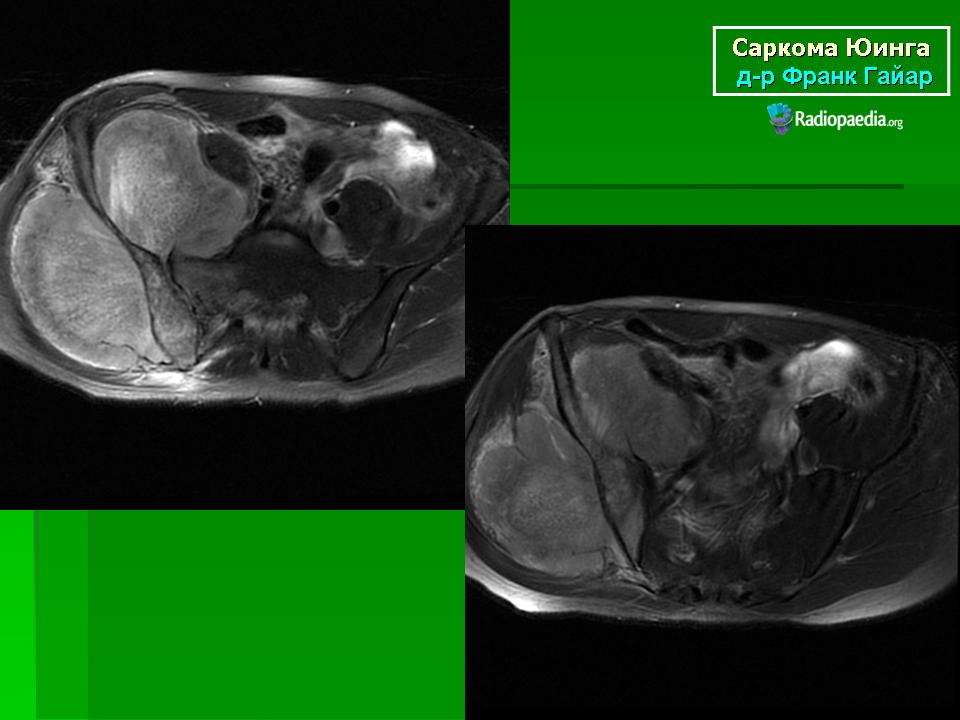

Для установления окончательного диагноза пациенту проводят компьютерную томографию или магнитно-резонансную томография костей и мягких тканей. Кроме того, выполняется ряд исследований для точной оценки характера новообразования.

Данные исследований КТ и МРТ позволят специалистам точно определить размеры новообразования, степень распространенности и поражение близлежащих тканей.

Чаще всего саркома Юинга выявляется в бедренной кости, костях таза, большеберцовой и малоберцовой кости, лопатке, ребрах, плечевой кости и позвонках. При возникновении в длинных трубчатых костях опухоль обычно локализуется в области диафиза, а затем по мере роста распространяется в сторону эпифизов. Более чем в 90% случаев отмечается интрамедуллярное расположение новообразования и тенденция к распространению опухолевых клеток по костномозговому каналу.

При выявлении типичных рентгенологических признаков саркомы Юинга больного направляют в отделение онкологии, где проводится расширенное обследование для оценки состояния первичного очага и выявления метастазов. В ходе такого обследования выполняется компьютерная томография или магнитно-резонансная томография костей и мягких тканей, пораженных злокачественным процессом.

Данные исследования позволяют точно определить размер новообразования, степень его распространения по костно-мозговому каналу, связь с сосудисто-нервным пучком и окружающими тканями.

Магнитно-резонансная томография (МРТ) дает дополнительную информацию относительно состояния костного мозга, мышц и соединительной ткани вокруг пораженных костей и помогает определить степень распространения опухоли.